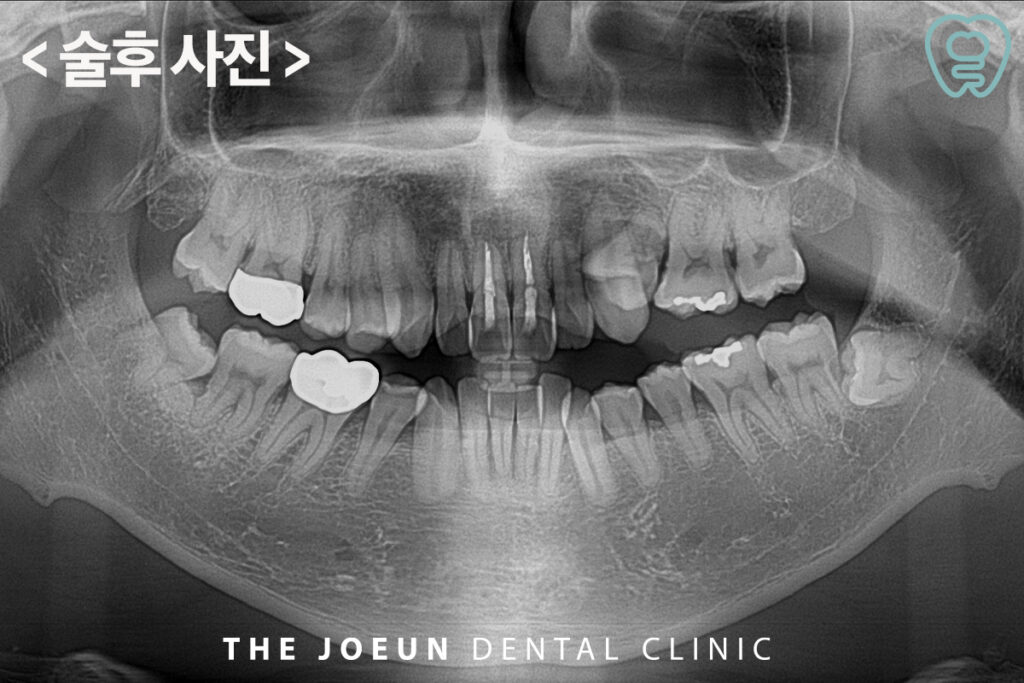

다음으로 낭종이 제거된 빈 공간에 뼈이식재를 채워줍니다. 뼈의 빈 공간이 큰 경우 특히 앞니의 경우라면 뼈가 주저 않는 경우가 있어 뼈이식이 필요합니다.

이어서 봉합을 한 후, 장치를 장착해 드렸습니다. 환자분께서는 붓기와 통증이 사라졌고 하나도 아프지 않다고 하시며 정말 감사하다며 밝게 웃으셨습니다.